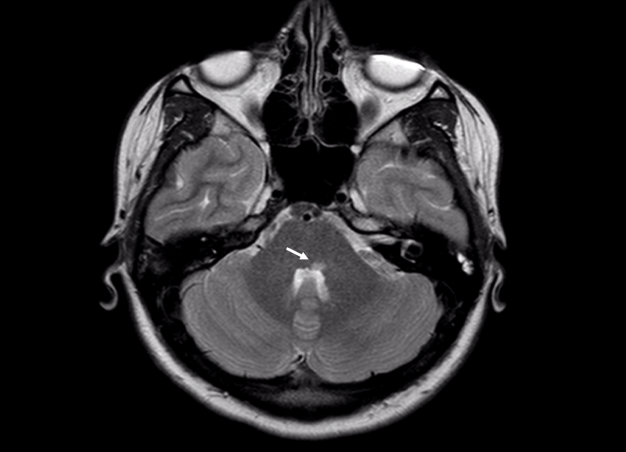

En estas imágenes se puede observar en la figura 1. una lesión localizada en el suelo del IV ventrículo, en la teórica localización del VI par craneal. El núcleo del VII par craneal se encuentra por delante e inferiormente, de ahí emergen las fibras motoras que realizan un recorrido ascendente y posterior «abrazando» al núcleo del VI par craneal. En la figura 2. en azul aparece el VI par craneal y en rojo está el «teórico» recorrido del VII facial.

En este caso el paciente acudió a urgencias para consultar por una pérdida de movilidad de la hemicara izquierda «periférica» y en la exploración presentaba una diplopía (visión doble) por afectación del VI par craneal. La naturaleza de la lesión fue inflamatoria y se diagnosticó posteriormente de Esclerosis Múltiple.